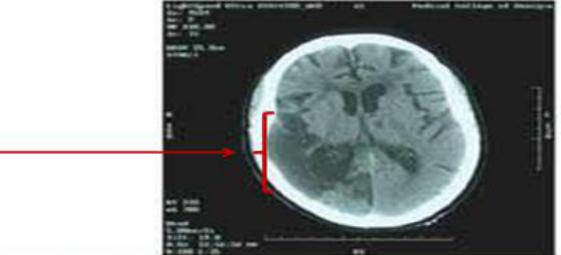

血液涂片检查、血红蛋白吸收光谱和脑部CT扫描的结果如图1-3所示。

图31、该患儿最有可能的诊断是什么?____?

患者的最终诊断为镰状细胞性贫血,并发右侧脑卒中。